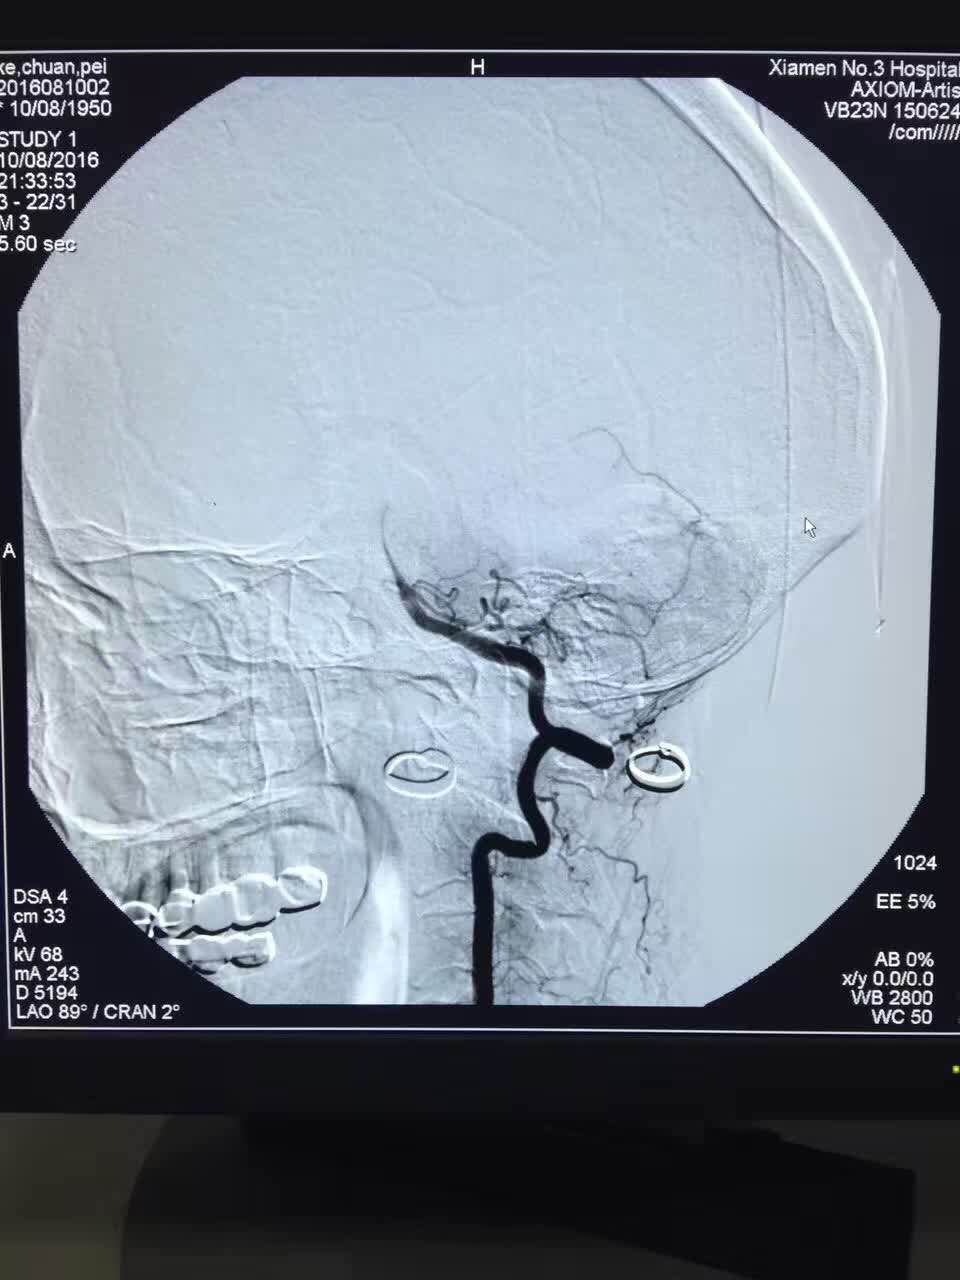

接诊后,经体检及急诊CT检查,诊断患者为严重的脑卒中(脑血管堵塞)。24小时待命的脑卒中治疗团队立即到院接诊病人。神经内科许文勇团队评估后,立即给予药物溶栓治疗,但药物完全进入体内后,观察半个小时,陈女士右侧肢体肢力仍无明显好转,表明血管堵塞严重,药物已无法溶解疏通。如果在治疗时间窗(8小时)内血管无法打通,病人将产生极为严重的后果。此时的关键是尽快打通堵塞的血管,必须采用高新技术动脉介入取栓方能解决。为此,神经外科陈金龙团队迅速将病人转入导管室进行脑血管造影,确定脑堵塞的部位,发现陈女士为颅内左侧大脑中动脉完全闭塞,即予以动脉介入取栓,介入医生将一个微导管和微导丝反伸入患者的右侧股动脉,反复“疏通”闭塞部位,用球囊在血管狭窄处扩张成形后置入支架。微导管前端有一个可以开合的“网兜”,当微导管伸至血栓处时,打开“网兜”。此时血栓就会附着在网兜上。把微导管往回拉,血栓就被拉出血管。介入医生连续“撒网”数次,取出长度约2厘米的血栓。当天夜里,陈女士的右侧肢体肌力完全恢复,在及时有效的治疗下,术后恢复状况良好,没有留下任何后遗症。